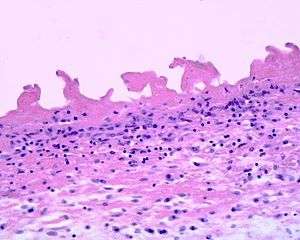

Fibrinous pericarditis is an exudative inflammation. The pericardium is infiltrated by the fibrinous exudate. This consists of fibrin strands and leukocytes. Fibrin describes an amorphous, eosinophilic (pink) network. Leukocytes (white blood cells; mainly neutrophils) are found within the fibrin deposits and intrapericardic. Vascular congestion is also present. Inflammatory cells do not penetrate the myocardium (as is seen with other presentations of pericarditis), and as a result, this particular variant does not present with diffuse ST elevation on ECG (a classic sign of pericarditis known as stage I ECG changes which are seen with other etiologies).[1] To naked eye examination, this pathology is referred to as having a "Bread and Butter Appearance".